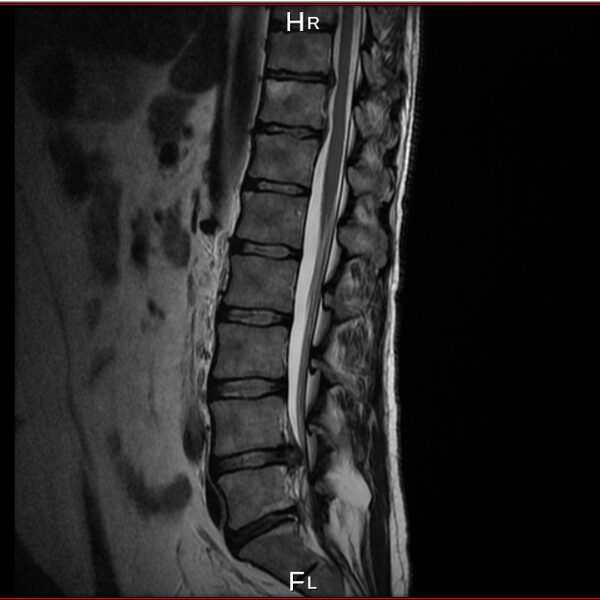

I have a lower spine problem, herniated disk and was using acupuncture (acupuncture is really good to control your musculus and controlling you like a robot) treatments with a Chinese doctor, first time all was perfect, but second time looks like happen mistake, you will be able to see this on pictures from private MRI scan– nuclear magnetic resonance that I have organised for myself. My left leg was just bone and skin, I lost all the musculus, because was not able to feed the main nerve responsible for keeping the proper function of the whole leg – I was parallelized. Pain is 24/7, 10 out of 10. At Royal infirmary hospital Edinburgh where I was hospitalized was giving me crazy amount of pain killers and very strong, that never helped. The doctors at the hospital they did great job providing me with modern technology to prevent the rest of the disk to slipping out to obtain the so-called calcification. All NHS staff did great job looking after me there. By 98% of the Doctors from around the world that I have managed to contact told me, that I have to make operation and there is no chance this to be sorted out other way. Well I have spent six months from my life and thanks god I had the finance to do that, trying to avoid operation. I have meet the right people to help me and expand my knowledge and I managed to avoid operation. Thanks to nature too. This situation get me to start learning a lot for human being anatomy and physiology, also reflexology, trigger points, blood, tocsins, minerals, how brain is responsible and reacting and much more…